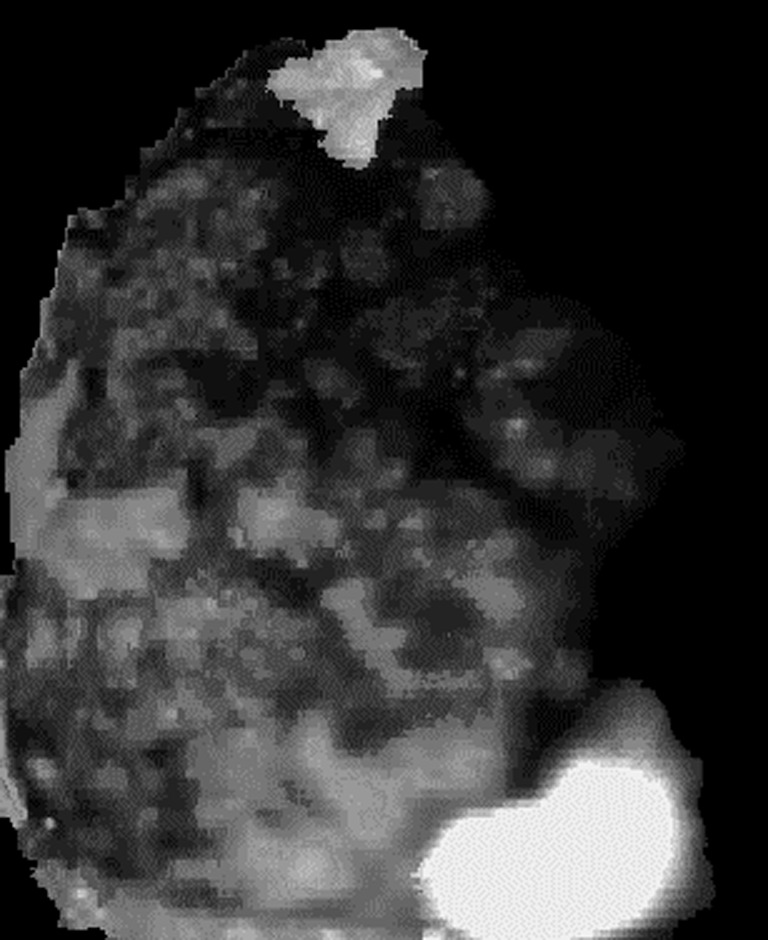

The constant α is a scale factor to ensure Ifused is within [0,255]. Using Eq. 2, through simple arithmetic operation containing addition and subtraction of the four narrow-band spectral images, one single fused image Ifused could be obtained. Every single exposure or frame of the MSI system corresponds to such a fused image. One fused image is shown in Fig. 7.

Fig. 7.

Exemplar fused image generated by the SNBI video camera